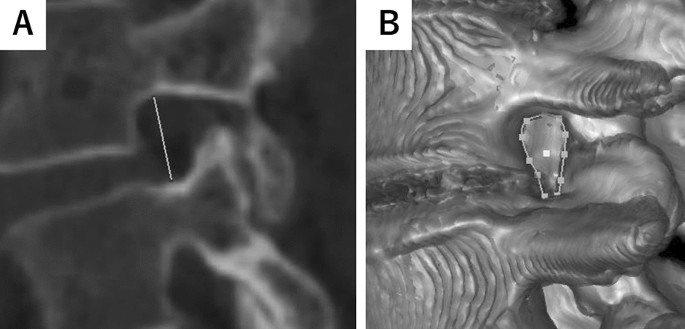

FH

FH is defined as the maximum distance between the lower edge of the superior pedicle and the upper edge of the inferior pedicle in the sagittal plane, we pointed out the bottom center and top center of the pedicle and measured the distance (Fig. 1A)14.

Representative image of foraminal height and bone boundary area. (A) Representative Axial View of L4/L5 Foramen. The solid line shows the foraminal height (FH). FH is defined as the maximum distance between the lower edge of the superior pedicle and the upper edge of the inferior pedicle. (B) 3D Reconstruction of L4/L5 Foramen. Dotted circle indicates the bone boundary area (BBA) of the foramen. BBA is defined as the area enclosed by the posterior edge of the vertebral body, the lower edge of the superior pedicle, the anterior edge of the inferior articular process, the anterior edge of the superior articular process, and the upper edge of the inferior pedicle.

BBA

BBA is defined as the area enclosed by the posterior edge of the vertebral body, the lower edge of the superior pedicle, the anterior edge of the inferior articular process, the anterior edge of the superior articular process, and the upper edge of the inferior pedicle. Due to rotation of the vertebral body altering the positions of the anterior and posterior edges when defined in the sagittal plane, we instead assessed the area on the plane formed by the axis of the FH and the axis of the inferior pedicle. We referred to a 3D model created by Zed View and adjusted the area enclosed by the bone to define the BBA (Fig. 1B)15.